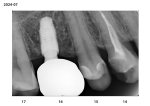

image.png

>>308095859

Номера зубов ебана.

>>308097098

>>308097117

27 и 47 у меня подозрения на воспалительный процесс, их бы пролечил, по остальным делать только в случае либо эстетический пломбы либо исправления прикуса/механики сцепления зубов